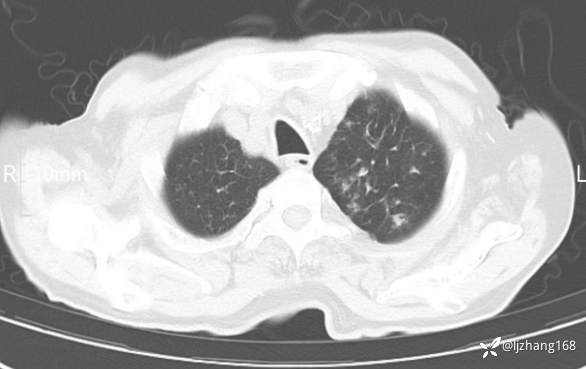

辅助检查:胸部CT:双肺肺气肿,间质性病变,血气分析:PH 7.413, PCO2 29.2mmHg, PO2,81.8mmHg,乳酸 3.3mmol/1,剩余碱-4.0mmol/1,HC03 18.8mmol/1。全血超敏C反应蛋白:超敏C反应蛋白 135.60 mg/L、 白细胞 14x19^9/L,中性粒细胞11.6x10^9/L。